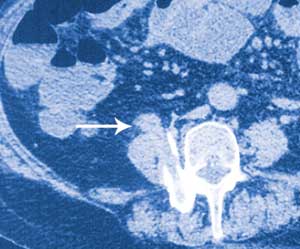

C Computed tomography scan

C: A loop of terminal ileum is in continuity with the anterior surface of the right psoas muscle (arrow), directly in line with the bony tract created by the glass fragment.

The abdominal radiograph was reviewed the day after clinical presentation and surgery. It was noticed that there was partial bony fusion of the right transverse processes of the fourth and fifth lumbar vertebral bodies. A CT scan confirmed that new bone formation at this level had produced a solid block of bone with a central defect in the shape of a rectangle. It is thought that the glass fragment snapped off deep to the skin and fractured the right transverse processes of L4 and L5, with the subsequent fracture healing process giving rise to a perfect bony cast of the fragment. It is well documented that a fracture initiates a sequence of inflammation, repair and remodelling, and that the remodelling process continues for years.1 Another CT scan showed the bony tract caused by the glass fragment projecting anteriorly into the right psoas muscle. Directly anterior to this, the terminal ileum could be seen lying on the anterior surface of the right psoas muscle (Figure, C). It is thought that the sharp end of the glass fragment gradually worked its way out the front of the psoas muscle and into the terminal ileum.